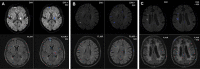

Introduction: When time since stroke onset is unknown, DWI-FLAIR mismatch rating is an established technique for patient stratification. A visible DWI lesion without corresponding parenchymal hyperintensity on FLAIR suggests time since onset of under 4.5 h and thus a potential benefit from intravenous thrombolysis. To improve accuracy and availability of the mismatch concept, deep learning might be able to augment human rating and support decision-making in these cases.

Methods: We used unprocessed DWI and coregistered FLAIR imaging data to train a deep learning model to predict dichotomized time since ischemic stroke onset. We analyzed the performance of Group Convolutional Neural Networks compared to other deep learning methods. Unlabeled imaging data was used for pre-training. Prediction performance of the best deep learning model was compared to the performance of four independent junior and senior raters. Additionally, in cases deemed indeterminable by human raters, model ratings were used to augment human performance. Post-hoc gradient-based explanations were analyzed to gain insights into model predictions.

Results: Our best predictive model performed comparably to human raters. Using model ratings in cases deemed indeterminable by human raters improved rating accuracy and interrater agreement for junior and senior ratings. Post-hoc explainability analyses showed that the model localized stroke lesions to derive predictions.